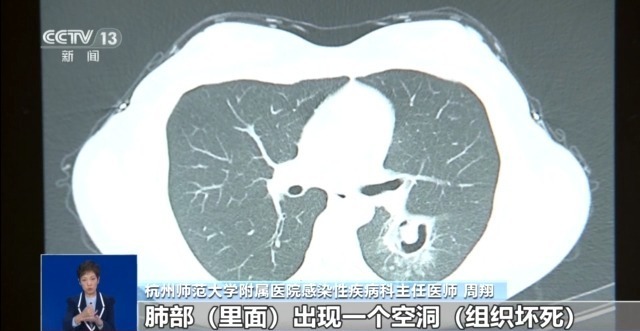

杭州师范大学附属医院感染性疾病科主任医师 周翔:肺部(里面)出现一个空洞(组织坏死),做支气管镜进行细菌检测,检测出来考虑是霉菌感染(霉菌性肺炎),后来我们就用正规的抗菌治疗。前天来门诊复查,我们给她再做了个CT,她这个病灶已经明显缩小,基本好了。